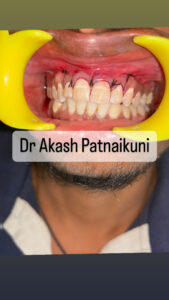

⦿ Gum Surgeries (Specialist/Consultant)

. Scaling and root planning

. Smile corrections